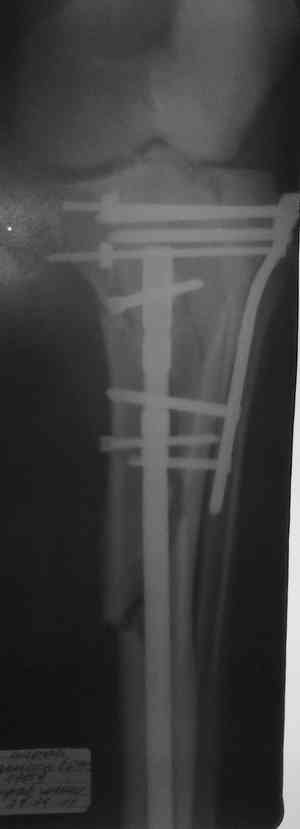

Скажите пожалуйста что навело на такой синтез? Выбрали не самый лучший способ фиксации-штифт и пластина? 2 противоположных методики.

Такой выбор обусловлен "плохим" состоянием мягких тканей в нижней трети голени. К тому же пациент гиперстеник и открытая методика нами сочлась не совсем удобной.

Чем одним??? Использование штифта не решит проблемы - перелом затрагивает мыщелки и проходит еще на уровне бугристости. Использование пластины на длинной ножке даже при подкожном введении предполагает высокую травматичность на фоне сохраняющегося отека. А так - 3 см разрез для штифта и 10 - для пластины.

Способ фиксации сам по себе - вполне приемлемый. Однако фиксации должна предшествовать репозиция.

Боюсь, задача восстановления формы суставной поверхности tibia осталась нерешенной.

Имелась центральная компрессия. Проводилась артротомия - суставная линия полностью восстановлена. Произведу контрольные рентгенограммы для доказательства.

Владимир! С Ваших слов ткани"плохие" в нижней трети, а перелом намного "выше", тем более блокировать штифт в нижней трети.И по поводу травматичности -у Вас получилось поболее ее. В принципе Вы достигли результата-"собрали перелом". Я бы сделал-1 опорной пластиной. Если была импрессия плата чем замещали дефект? Просто на снимке не видно.

Решили выполнить остеосинтез штифтом и внутрисуставного перелома пластиной и винтами. Жду мнения! Зачем мне оправдываться-я же не преступник. Диалогом называется...

Отдельные переломы тибиал плато и перелом проксимальной трети большеберцовой кости отличаются от переломов тибиал плато с вовлечением диафиза. Здесь перелом тибиал плато типа Schatzker VI, полученный в результате высокоэнергетической травмы. Перелом метафиза образовал отрыв суставной поверхности от диафиза с вовлечением медиального и латерального мыщелков. Двухмыщелковые переломы из-за укрочения опасны развитием компартаментального синдрома, повреждением латерального мениска и связок.

Одна из проблем фиксации тибиал плато - это предупреждение мягкотканых осложнений, и это достигается проведением поэтапной фиксации. Такая тактика - первым этапом дистракция любым наружным фиксатором, а затем по готовности кожных покровов и после спадения отека операция. Операция в ранние сроки и без адекватной готовности кожных покровов лимитирует ваши действия опасностью осложнении, но без адекватного доступа фиксация получается ущербная. Для предупреждения осложнений лучше подождать и в зависимости от серьезности травмы можно ожидать иногда от 1 до 2 недель.

При переломах одного из мыщелков тибиал плато+дополнительный перелом проксимальной трети большеберцовой кости можно применить комбинированный вариант фиксации, т.е. мыщелок винтами или пластиной, а для диафиза можно установить гвоздь. В данном варианте потеряно преимущество гвоздя , из-за серьезной травмы суставной поверхности нельзя нагружать ногу несколько месяцев. А без нагрузки гвоздь просто заполнитель пространства внутри кости!

На вашем место я бы подождал с фиксацией до готовности кожных покровов, и за это время можно было подобрать соответствующий фиксатор, т.е более длинная пластина снаружи и медиальная пластина на апексе перелома как подпорка. Здесь приемлем как раз минимальный доступ.

Имеющаяся импрессия не потребовала пластики - достаточным оказалось поднять отломок

Если там действительная импрессия, пустое место без структуральных заполнителей, кость или синтетические материалы, не восстановится, а образуется коллапс, и ось конечности поведет после нагрузки. Кроме того там возможно "болт стяжка"?, в медиальной стороне выступает за кортекс, можно было укоротить! Потом создается впечатление, что не соответствуют мыщелки большеберцовой и бедренной костей? Покажите снимок.

Ваша упорство с минимальными данными защищаться забавляет, и пока не все убедились в Вашей правоте. Для нормальной защиты необходимы аргументированные доказательства исследованиями. КТ сканы и прицельно сделанные снимки коленного сустава, а так все аргументы - не более чем "моя фиксация, мне нравится". Без этих доказательств пока только Ваше упорство.....